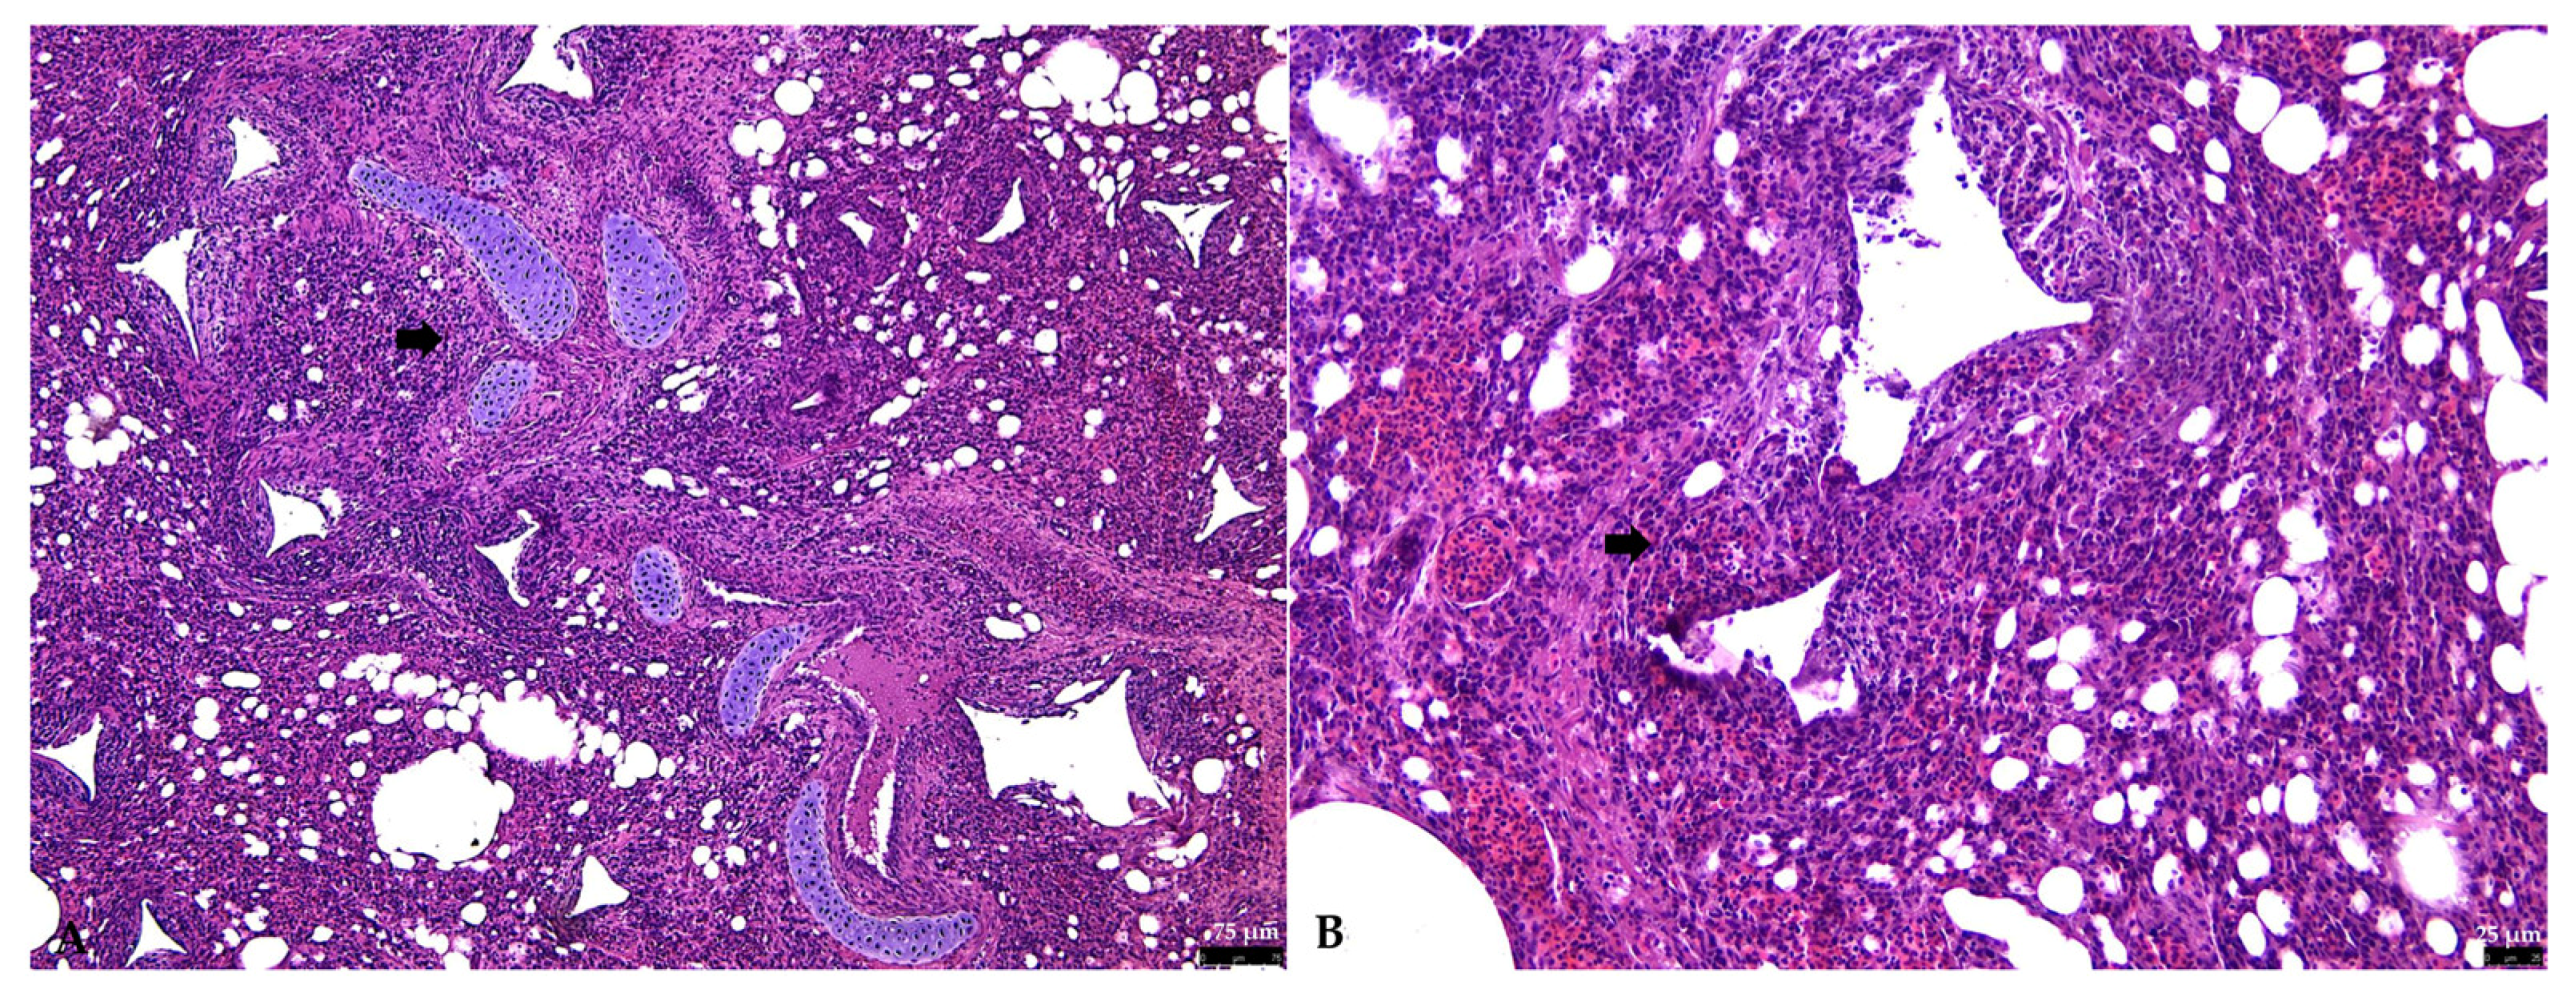

3.2. Histopathology

3.2.1. Respiratory Tract